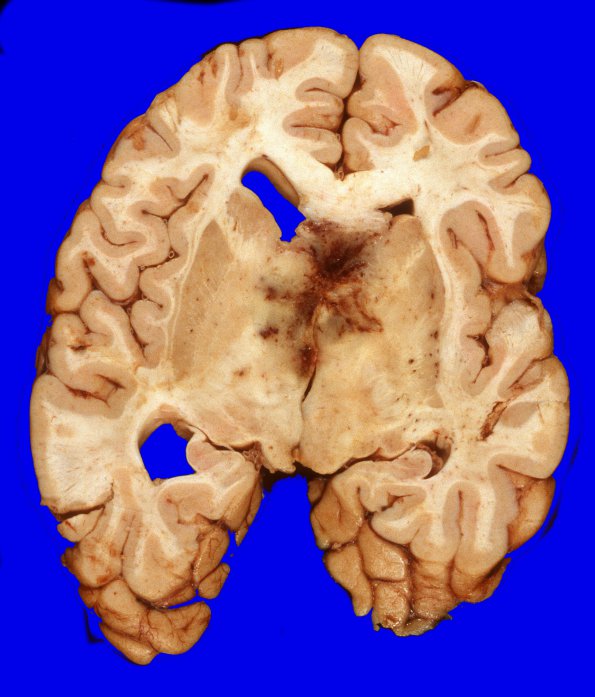

10A6,7 Continuity of the tumor with the thalami/basal ganglia bilaterally is established.